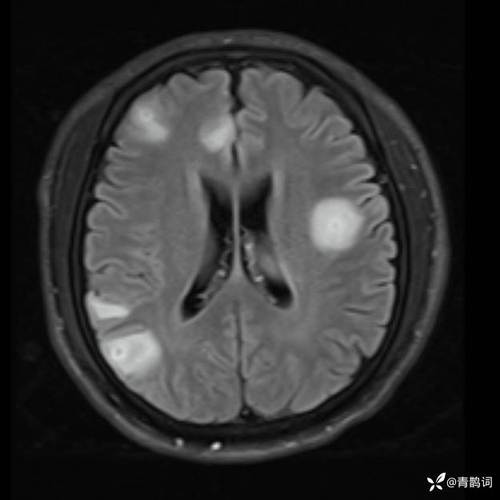

- “弥散受限”的含义:在MRI的“弥散加权成像”(DWI)序列上,如果水分子运动受限,无法自由移动,这个区域在图像上就会显示为高信号(亮白色),这就是“弥散受限”的影像表现。

- 急性期(<1周):病灶在DWI上呈高信号(亮),而在另一个序列“表观弥散系数”(ADC)图上呈低信号(暗),这个“亮-暗”组合是急性梗死的典型表现。